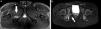

En general, se trata de roturas parciales en cualquier sitio del músculo (fig. 9). Las lesiones aisladas son poco comunes y suelen darse en deportistas de alto rendimiento (futbolistas), generalmente luego de descartar otras causas.

(a) Desgarro del obturador externo. La secuencia ponderada en STIR, plano axial, evidencia una rotura parcial a nivel de la unión miotendinosa adyacente a su inserción en el sector posterior del trocánter mayor (flecha). La consulta clínica fue por sospecha de desgarro de isquiotibiales. La ecografía resultó negativa. (b) Desgarro del obturador interno. La secuencia ponderada en T2 con supresión grasa, en plano axial, muestra una rotura fascicular (grado II) a nivel del vientre muscular con moderada cantidad de líquido y edema de partes blandas en topografía del pilar posterior del acetábulo adyacente a su inserción en el trocánter mayor (flecha).

La mayor parte de los casos publicados se trata de roturas parciales con marcado edema muscular y rotura de la aponeurosis entre el sóleo y el gemelo interno (fig. 13).

Desgarro del músculo sóleo. Las secuencias ponderadas en STIR, planos (a) axial y (b) sagital, detectan una rotura parcial a nivel de la unión miotendinosa proximal (flechas). La marcada cantidad de líquido interfascial corresponde a la rotura de la aponeurosis. El paciente no presentaba desgarro asociado del gemelo interno ni del plantar delgado.